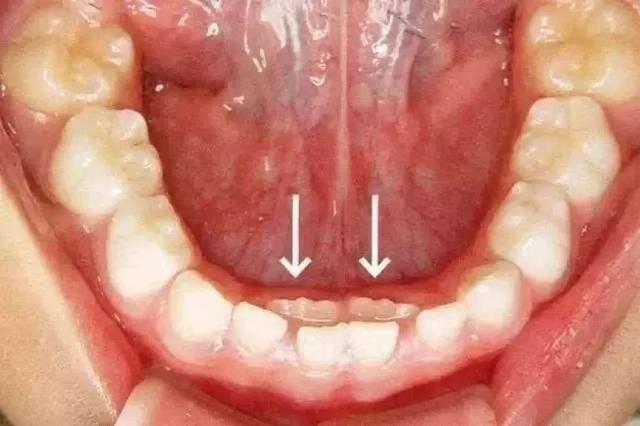

有的孩子长了双排牙,家人也迟迟没发现;

双排牙。图片来源:苏州口腔医院

有不少家长,就是因为不关注换牙顺序,平时也不检查孩子口腔,等到双排牙长出好一段时间了才发现,然后急匆匆地带孩子去医院拔牙……